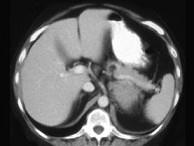

问题 女,47岁,满月脸、向心性肥胖伴高血压1个月,请结合所提供图像,作出诊断 ( )

选项 A、左肾上腺嗜铬细胞瘤 B、左肾上腺增生 C、左肾上腺腺癌 D、左肾上腺转移瘤 E、左肾上腺腺瘤

答案 C